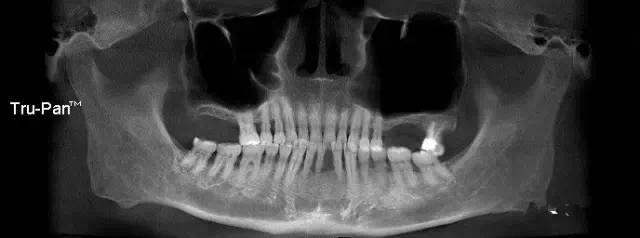

第二圖:上頜竇氣化,導(dǎo)致上頜竇很大,骨高度不足,但是上頜竇底平,粘膜很干凈。適合外提升或者高手可行內(nèi)提升。(還有二次內(nèi)提升)。